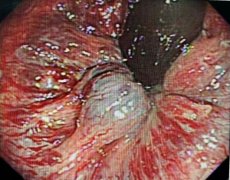

无痛 快速 解决痔疮丨陕西冶金医院技术--消化内镜下治疗痔疮!

俗话说十人九痔 在我国,痔疮发病率大约为87.5% 90岁的袁老太 一直都有难言之隐痔疮 但由于高年龄,同时伴高血压 冠状动脉粥样硬化性心脏病 等有多种慢性病 辗转多家医院治疗未果